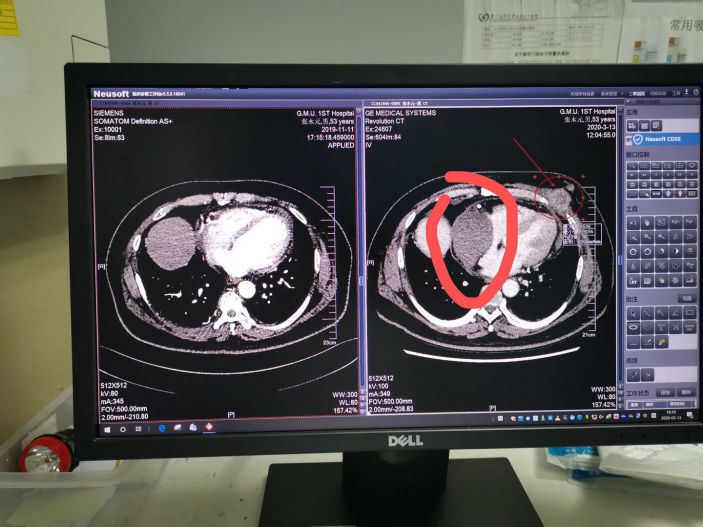

入院時,患者上腔靜脈及右心房右心室都被腫塊明顯擠壓,出現上腔靜脈綜合征,顔面浮腫端坐呼吸。入院後予下肢輸液,應用大劑量糖皮質激素及呋塞米治療後症狀稍減輕。

一開始患者家屬很不信任我們,但是有兩個巧合:第一個巧合是我去年去廣州參加一個介入會議回來的時候和患者同坐一個班次高鐵,一路上聊了很多,知道他是一個很豁達的人,也知道他在口服泰瑞莎之後我告訴他可以來我院辦理特殊門診,後來他也來辦理了特殊門診;第二個巧合是查房時,患者無意中說一個月前在我院門診複查過CT,我看了患者一個月前的CT片并沒有心包腫塊就感覺不對勁,因爲一個月内長這麽大的轉移瘤可能性很小。

于是我主動和患者在廣州的主管醫師溝通,他也覺得奇怪。爲了這個事,我先找我院影像科的胡主任看片,胡主任的意見是實性腫塊伴強化,考慮轉移可能性大,但是強化不是特别強,不能排除其它可能。我又找了超聲科陳主任做了一個心髒彩超,陳主任說超聲顯示是實性腫塊,但是腫塊回聲有不均勻,除了腫瘤以外有一個很小的可能是陳舊血腫,但是超聲下很難定位。患者在超聲科聽到我和陳主任的對話之後就說我現在生不如死,不能平卧,吃不下東西,他說李主任你放心去治,就算死了我也不怨你。我又請了胸外科張曉忠主任來會診,張主任也覺得一個月内長這麽大的轉移性腫瘤可能性不大,這進一步堅定我的判斷——這并非轉移瘤,而是心包内巨大血腫。

經CT定位,隻有一個間隙可以進針,我和外三科主任張曉忠一起上台穿刺,小心翼翼一針穿刺下去,出來的是黑色的血,證明我的判斷是正确的。引流出來後,患者的呼吸困難馬上就緩解了。術後患者終于能進食又能睡個安穩覺了。